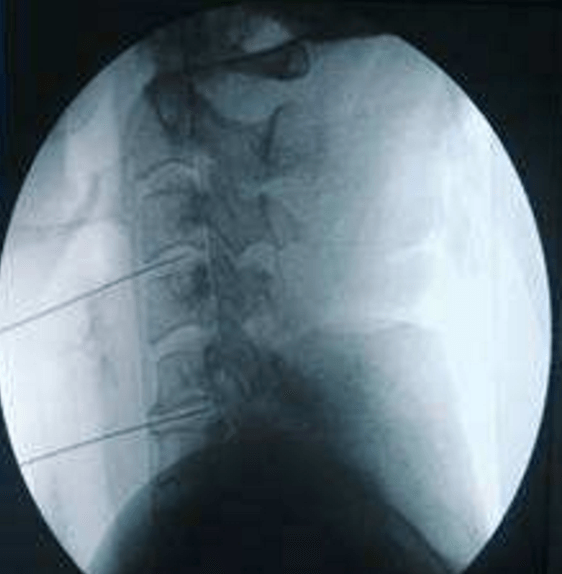

頸、腰椎間盤射頻微創(chuàng)手術

經過多年的發(fā)展,現在的延安大學咸陽醫(yī)院疼痛科在診療技術上已經達到一流的水平。尤其在頸、腰椎間盤突出微創(chuàng)治療方面,手術量居地區(qū)前列,脊柱壓縮骨折椎體成型術、頸、腰交感神經射頻調控微創(chuàng)手術、三叉神經痛、帶狀皰疹后神經痛以及外周血管介入、腫瘤微創(chuàng)介入、內臟出血等介入治療方面,為地區(qū)最優(yōu)秀的疼痛科之一。